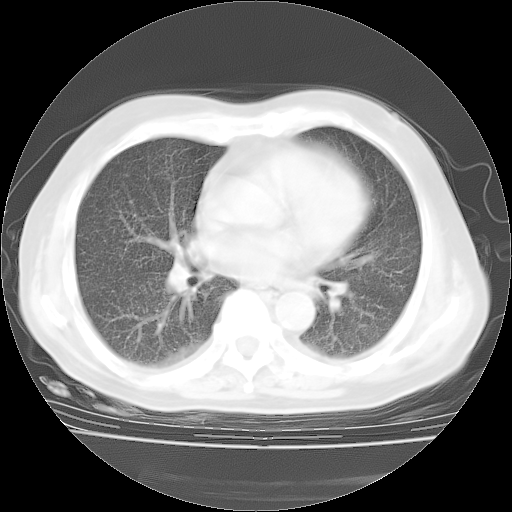

4月28日肺部CT——再次出现类似去年5月9日——透光度降低,“间质性”改变。

4月28日肺部CT——再次出现类似去年5月9日——磨玻璃样、间有“粟粒样”改变。

4月28日肺部CT